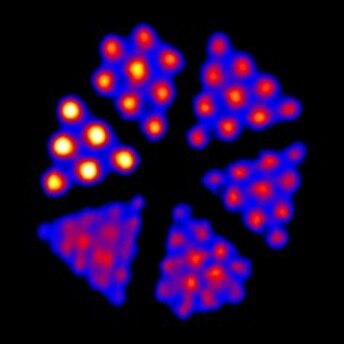

Phantech Derenzo模體是一種分辨率體模,具有不同大小的孔圖案。尺寸組中的孔的間距為2D(直徑的兩倍)。

只需確定給定的同位素和計(jì)數(shù)值即可分辨的最小孔組,即可啟用掃描儀的分辨率測試。我們的Derenzo模體具有六種不同的孔尺寸,它們圍繞模體以三角形排列。

Derenzo模體的示例圖像,包括在Bruker BioSpin MRI系統(tǒng)上成像的1.0 mm至1.5 mm模式Derenzo(上)和在Inveon PET / CT系統(tǒng)上成像的F-18成像的0.7 mm至1.5 mm模體(下)